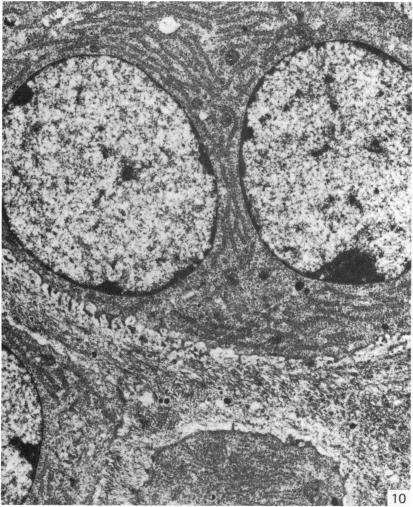

来自矮胖(stm)突变小鼠下颌髁突的异常软骨。

Abnormal cartilage from the mandibular condyle of stumpy (stm) mutant mice.

The mammalian mandibular condyle is composed of secondary cartilage and may thus be susceptible to genes causing achondroplasia and which result in abnormal++ primary cartilage formation. This paper describes the secondary cartilage in the mandible of the stumpy achondroplastic mutation in the mouse: both primary and secondary cartilage are affected by the gene.

哺乳动物的下颌髁由继发性软骨组成,因此可能易受导致软骨发育不全并致使初级软骨形成异常的基因影响。本文描述了小鼠短粗型软骨发育不全突变体下颌骨中的继发性软骨:初级软骨和继发性软骨均受该基因影响。